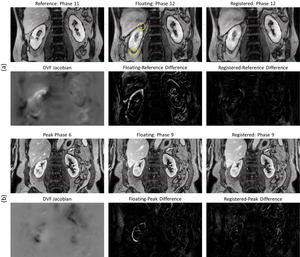

Motion Correction of the Kidneys in Long-Duration MRI Time Scans

4D MRIs of the kidneys are often acquired with long acquisition times, which can lead to motion artifacts. I built a two-stage, coarse-fine deep learning pipeline with convolutional neural networks and vision transformers to correct motion artifacts in kidney MRIs.

View Project | View Paper